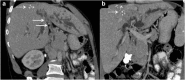

Methods: Indubitably, imaging is the mainstay for detection of tubercular hepatic lesions which display a broad spectrum of imaging manifestations on different modalities. While sonography and computed tomography (CT) findings have been described in some detail, there is a paucity of literature on magnetic resonance imaging (MRI) features. Due to a significant overlap with other commoner and similar appearing hepatic lesions, hepatic tuberculosis is often either misdiagnosed or labelled as indeterminate lesions. This article is a compendium of cases highlighting the spectrum of imaging patterns that can be encountered in patients with isolated primary hepatic tuberculosis as well as disseminated (secondary) disease. Rare patterns of primary disease such as tubercular cholangitis, hypervascular liver masses, and those with vascular complications are also illustrated and discussed.

Teaching points: • Hepatic TB has myriad imaging manifestations and is often confounded with neoplastic lesions. • Imaging patterns include miliary TB, macronodular TB, serohepatic TB and tubercular cholangitis. • Concurrent splenic, nodal or pulmonary involvements are helpful pointers towards the diagnosis. • Miliary calcifications along the bile ducts are characteristic of tubercular cholangitis. • Histological/microbiological confirmation is often necessary to confirm the diagnosis.